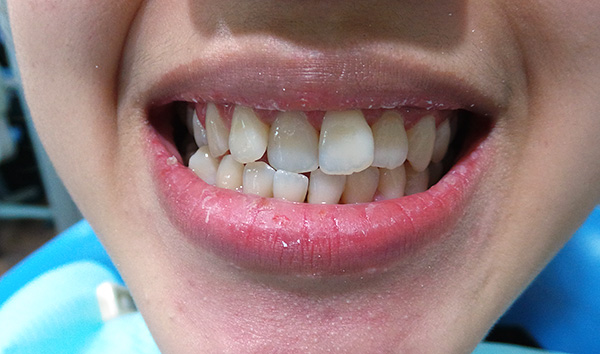

Um exemplo de mordida cruzada unilateral em um adulto:

Quanto à mordida cruzada bilateral, a causa mais comum dessa patologia é uma incompatibilidade no tamanho dos arcos dentários. Muitas vezes, isso é combinado com uma mordida patológica da classe II, de acordo com Engle, e a posição frontal da mandíbula superior, que às vezes requer tratamento com um cirurgião oral e maxilofacial para corrigir completamente a patologia.